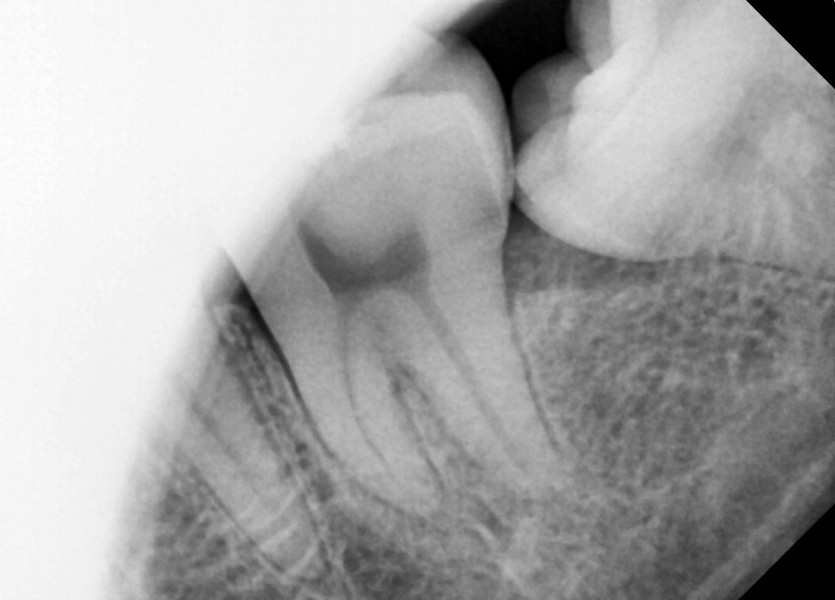

#28,38 사랑니 발치

구강 외과 전문의가 당일 발치했습니다.